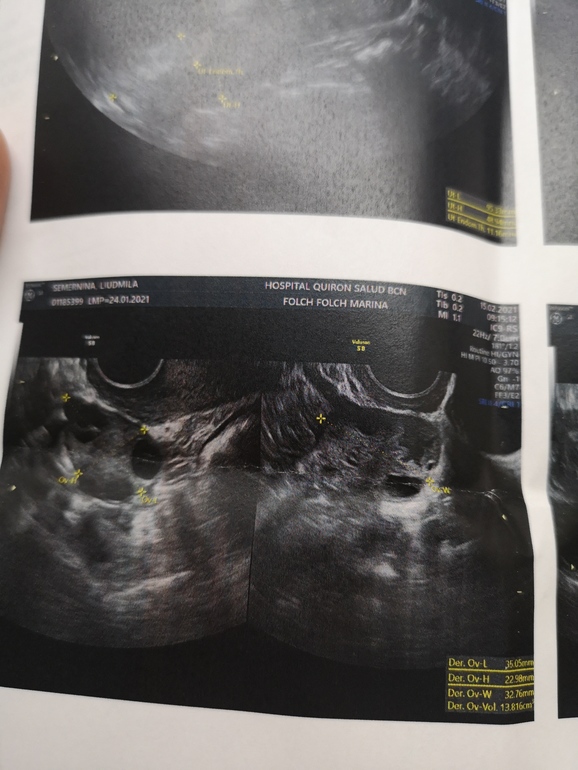

Фото скину, а заключение не на русском, не поймёте)) Единственное пя был увеличен в 2 раза, у меня так бывает там где дф или О, первая фото пя